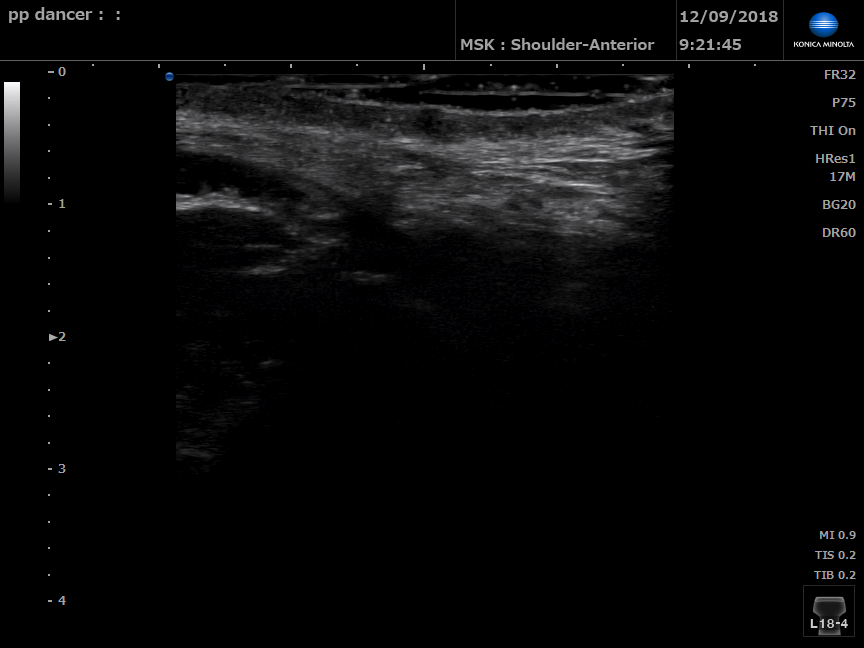

Dancer without pelvic floor dysfunction

B Mode ultrasound of left perineal body